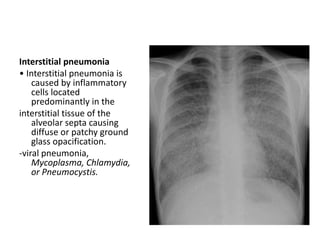

Interstitial pneumonia

• Interstitial pneumonia is

caused by inflammatory

cells located

predominantly in the

interstitial tissue of the

alveolar septa causing

diffuse or patchy ground

glass opacification.

-viral pneumonia,

Mycoplasma, Chlamydia,

or Pneumocystis.